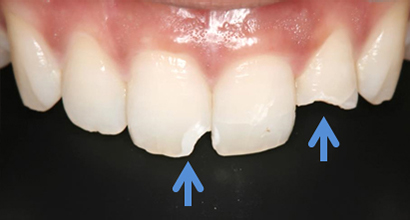

ダイレクトボンディング症例1

前歯がかけた

術前

転倒して前歯がかけてしまい(青矢印)できるだけ削らない治療ダイレクトボンディングを希望して来院されました

ダイレクトボンディング治療後